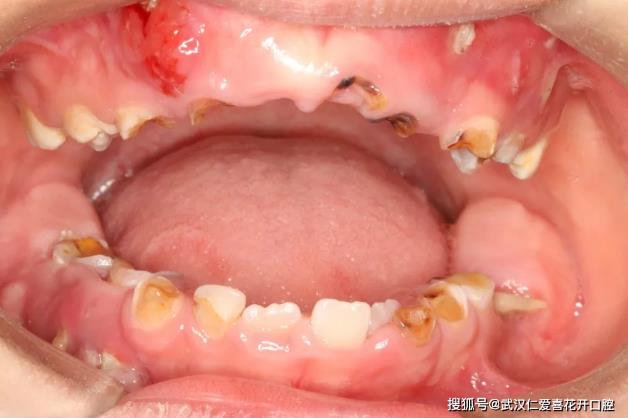

首先,我們先來看一張令人痛心的圖片。

這是一名4歲男孩瑞瑞的口內照片,從照片里面可以看出,瑞瑞幾乎全口都是蛀牙,大部分牙齒僅剩殘冠。為什么會出現這種情況呢?瑞瑞爸無奈的說道,瑞瑞有睡前喝奶的習慣,經常含著奶瓶就睡著了,也不愛刷牙,家人也沒多加約束,所以在兩歲的時候,就開始有了蛀牙。瑞瑞家人認為,孩子乳牙蛀了沒關系,反正會換新牙,就這樣一直沒有重視。結果到了近日,瑞瑞蛀牙情況越發嚴重,還經常出現酸痛腫脹等癥狀,這才帶他前來家附近武漢仁愛口腔醫院就醫。

專治兒童口腔楊醫師給瑞瑞做了口腔檢查后告知,瑞瑞的這種短時間內形成多個進展迅速的滿口齲齒叫“猛性齲”又稱猖獗齲。與含奶瓶入睡、喝夜奶、不良口腔衛生習慣等因素有關,多見于兒童初萌牙列和頭頸部放射線治療或患嚴重口干癥的成年人。

“猛性齲會導致短期內多個牙面同時患齲、并迅速進展,累及口腔內大多數牙,造成大面積齲壞,甚至很快進展到牙髓引起牙髓及根尖炎癥,在兒童群體里越來越常見。”楊醫師指出,在睡覺時,人的口腔唾液分泌會減少,牙齒自潔能力減弱,如果孩子含奶瓶入睡或喝夜奶后不及時刷牙,牙齒就會長時間處在含有大量乳糖、蔗糖等碳水化合物的唾液微環境中,細菌易滋生繁殖,就會造成牙齒脫礦,形成蛀牙。此外,如果發現蛀牙不及時治療、口腔衛生狀況不好等,也會導致口腔內細菌越積越多,在細菌、飲食、牙和唾液等共同因素作用下,就易導致“猛性齲”的發生。

經檢查發現,瑞瑞的口腔狀況不容樂觀。20顆牙齒中,有2顆深齲,有11顆牙齒僅剩殘冠,牙根完全吸收。還波及到繼承恒牙胚的發育、礦化,鈣化,會導致日后新牙萌出后會出現發育不全發育異常等情況。此外,瑞瑞右下有2顆牙齒有嚴重根尖炎癥,造成牙槽骨骨質破壞,如果不盡早處理,這個骨質破壞會繼續下去,可能會導致頜骨間隙出現感染,引起頜骨的骨髓炎。

同時,瑞瑞下門牙有2顆乳牙因齲壞嚴重而過早缺失,導致恒牙過早萌出,這2顆“提前上崗”的恒牙,牙根目前仍處于未發育完善的狀態,這會導致日后恒牙松動,容易脫落。

楊醫師指出,猛性齲危害大、發展迅速。不僅會直接造成乳牙缺損,繼而發展為牙髓病、根尖周病,甚至可能會導致孩子牙齒早失,影響孩子的咀嚼、消化系統的正常功能,影響恒牙的萌出,使繼承恒牙發育異常。此外,乳牙早失還可能會導致恒牙萌出的正常時間、順序和位置異常,出現換牙后的牙齒不齊,也直接影響美觀,甚至影響吐字發音,孩子的自尊心和自信心很容易受到打擊,給孩子身心健康造成不可逆的傷害。